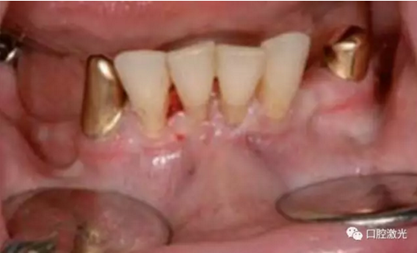

下唇系帶整形手術(shù)前

術(shù)后即刻

術(shù)后3天